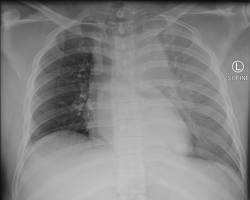

- Pneumothorax (collapsed lung): This occurs when air leaks into the space between the lung and chest wall, causing the lung to collapse.